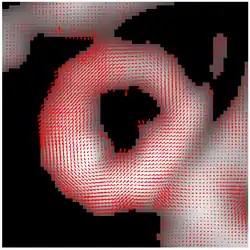

Result of HARP tracking of a tagged cardiac MRI slice

The result of HARP tracking of one frame of cardiac MRI is shown in the figure. It is obtained by calculating both motions from horizontal direction and vertical direction, resulting in a 2D vector field showing the motion of every material point on the myocardium at this time frame.